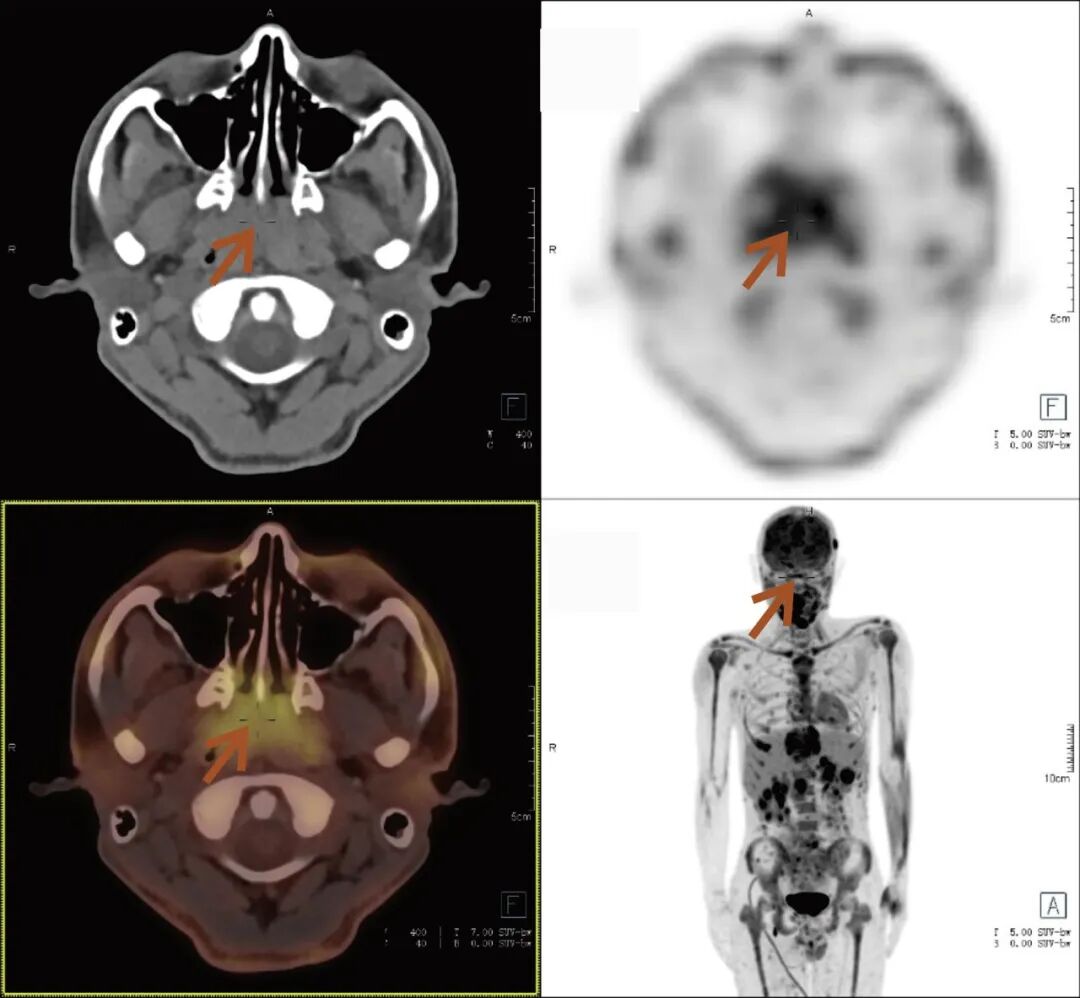

张先生(化名),因持续3个多月的腹痛、腰痛在外院就诊。初始CT检查发现其胸11椎体骨质破坏伴周围软组织肿胀,考虑为“脊柱结核”等感染性病变,并接受了中药治疗。然而,两个月后,张先生又出现了新的症状——牙痛。 经病理活检及免疫组化检查,最终确诊为极为罕见的Erdheim-Chester病。为全面评估这一可累及全身多系统疾病的侵犯范围、明确病灶活动性,并为制定精准治疗方案提供依据,张先生进行了全身PET/CT检查。 PET/CT检查图像: PET/CT检查结果: (1)中轴骨及四肢骨广泛FDG代谢活跃伴信号异常;其中胸10、胸11椎体病灶周围软组织增厚,累及邻近椎管内及双侧椎间孔、双侧胸膜,并与主动脉分界不清。 (2)全身皮下及肌层内多发结节及肿块,FDG代谢活跃;全身软组织广泛肿胀。 (3)鼻咽各壁增厚,顶后壁为著,FDG代谢活跃。 (4)甲状腺多发结节,FDG代谢活跃;双肾及胰腺多发结节及肿块,FDG代谢活跃;双侧阴囊内异常信号伴FDG代谢活跃; (5)左侧锁骨上窝、纵隔内(2L区、3A区)、降主动脉旁、左侧横膈前组、右侧腋窝、左肾周间隙、肠系膜区、双侧髂血管旁多发淋巴结,FDG代谢活跃; (6)心包局部呈结节状稍增厚,FDG代谢轻度活跃; 综上,结合临床,均考虑Erdheim-Chester病所致。 此次PET/CT不仅证实了已知的脊柱病变,更一次性揭示了临床尚未怀疑的、广泛存在于内脏、淋巴结及软组织的隐匿病灶,为疾病分期与治疗提供了决定性依据。